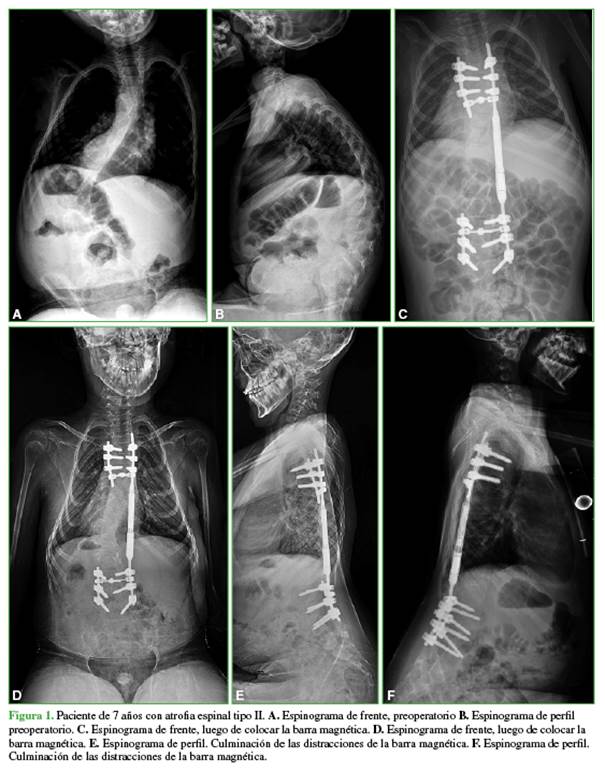

Se evaluó a 37 pacientes, 19 niñas y 18 niños, con una edad promedio de 8.2 años en el momento de la cirugía (rango 4-12). Las etiologías de la ECT eran: escoliosis neuromuscular (atrofia medular espinal, miopática, encefalopatías crónicas no evolutivas) (17 pacientes), escoliosis sindrómica (Silver-Rusell, William, Prader-Willi, Escobar, Marfan, neurofibromatosis, genéticos, displasia esquelética) (14 pacientes), escoliosis idiopática infantil (3 pacientes), escoliosis congénita (3 pacientes) (Figura 1).

Se dividió a los 37 pacientes en dos grupos: grupo 1 (n = 28), aquellos sometidos inicialmente a tratamiento con el sistema de BM, la edad promedio al operarse era de 8.1 años (rango 4-12), con un seguimiento promedio de 3.1 años (rango 1-6), desde 2014 hasta 2020.

En el grupo 1, el valor angular promedio de escoliosis era de 64° (rango 39°-101°) antes de la cirugía, y de 41°(rango 17°-80°) en el posoperatorio inmediato. El valor angular promedio de cifosis preoperatorio era de 51° (rango 22°-111°) y de 34° (rango 7°-82°) en el posoperatorio.

La distancia preoperatoria registrada promedio T1-T12 fue de 147 mm (rango 95-190) y de 169 mm (rango 104-217) en el posoperatorio inmediato. La distancia preoperatoria promedio T1-S1 era de 253 mm (rango 205-288) y de 306 mm (rango 215-354) en el posoperatorio inmediato (Tabla 1).